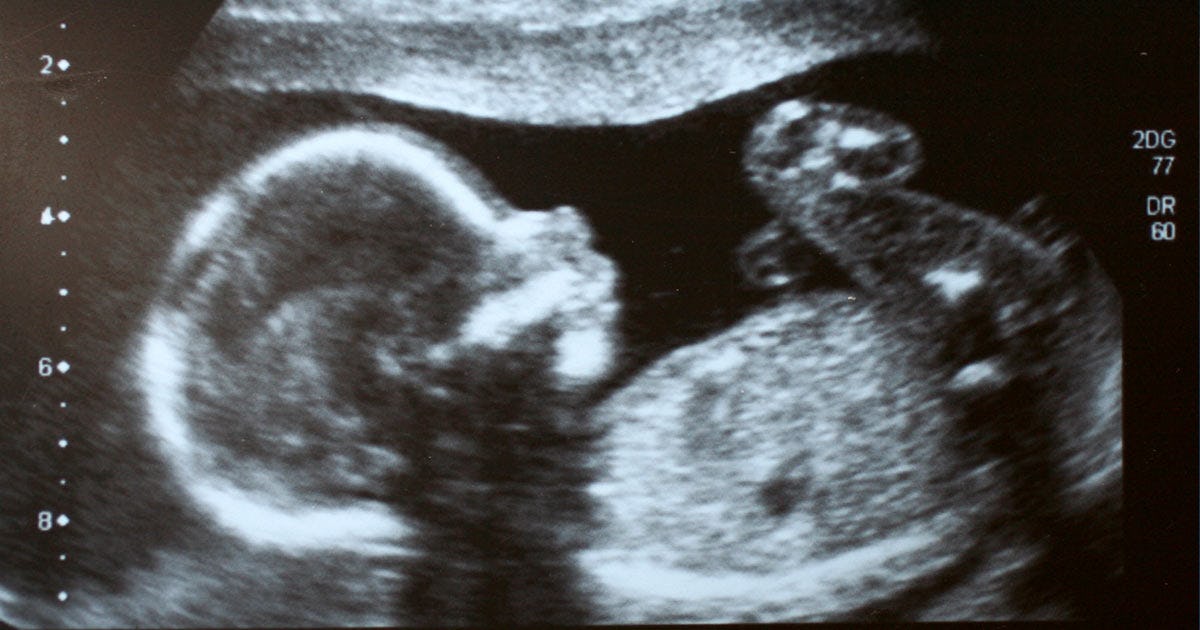

Fetal Hiccups Why Do Babies Get Hiccups In The Womb

Hiccups are a reflex that happens when the diaphragm muscle contracts and relaxes too quickly. As mentioned above the diaphragm is a muscle that aids breathing and a fetus hiccups are caused by the contraction of this muscle. If your baby hiccups while still at the breast hell most likely stop feeding since the hiccups can be uncomfortable at that point.